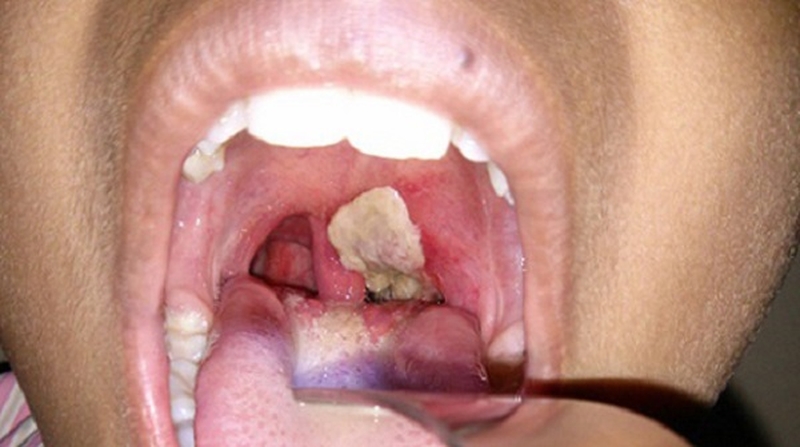

Hình ảnh viêm amidan giả mạc

Bệnh chỉ chiếm khoảng 2 – 3% nhưng lại vô cùng nguy hiểm. Quan sát vòm họng, bạn có thể dễ dàng thấy:

• Cả 2 amidan sưng to đỏ thẫm, các khe bị giãn ra và bị lớp bựa trắng bao phủ ở khe miệng.

• Lớp bựa trắng có tính chất dày, dai, bám chặt vào niêm mạc họng, amidan. Sau đó lan rộng, một số trường hợp lan xuống thanh quản gây khó thở ở người bệnh.

• Hạch vùng sau góc hàm sưng to, đau, khó chịu.